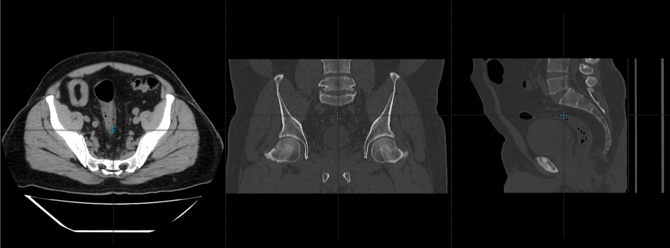

¿Cómo visualizar el mismo punto anatómico en diferentes planos en el visor web?

Te mostraremos la herramienta que permite situar un punto anatómico en todos planos

1. Selecciona la herramienta de triangulación

que encuentras en la parte superior del visor.

2. La cruz de color azul te permitirá con un clic izquierdo sostenido desplazar el mouse e ir visualizando el mismo punto anatómico o nivel de corte en los tres planos.